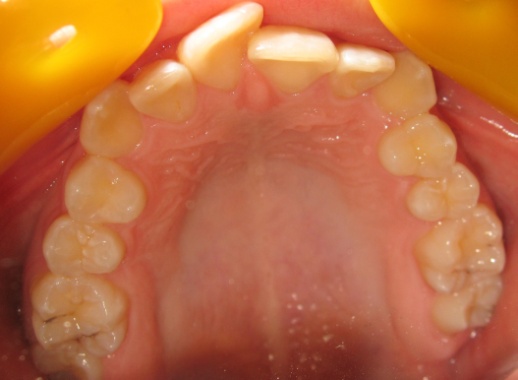

3 - Vues occlusales avec espaces d’extraction

Les vues occlusales montrent les espaces d’extraction des prémolaires au début du traitement, puis leur fermeture progressive. Les dents antérieures encombrées ont été alignées grâce au recul des canines dans ces espaces, sans déplacement des incisives centrales. La face vestibulaire de ces dernières est restée inchangée, préservant ainsi les rapports entre la lèvre supérieure et les incisives avant et après traitement. Les extractions n’ont donc pas entraîné de recul global, mais simplement créé la place nécessaire.